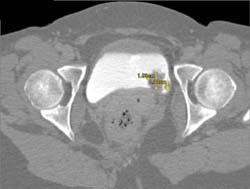

Diagnosis

Bladder Cancer